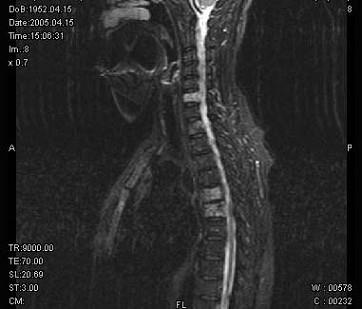

请结合提供图像,选择最佳选项 ( )A、退行性变B、脂肪瘤C、多发性骨转移D、骨血管瘤病E、骨结核

问题 请结合提供图像,选择最佳选项 ( )

选项 A、退行性变 B、脂肪瘤 C、多发性骨转移 D、骨血管瘤病 E、骨结核

答案 D